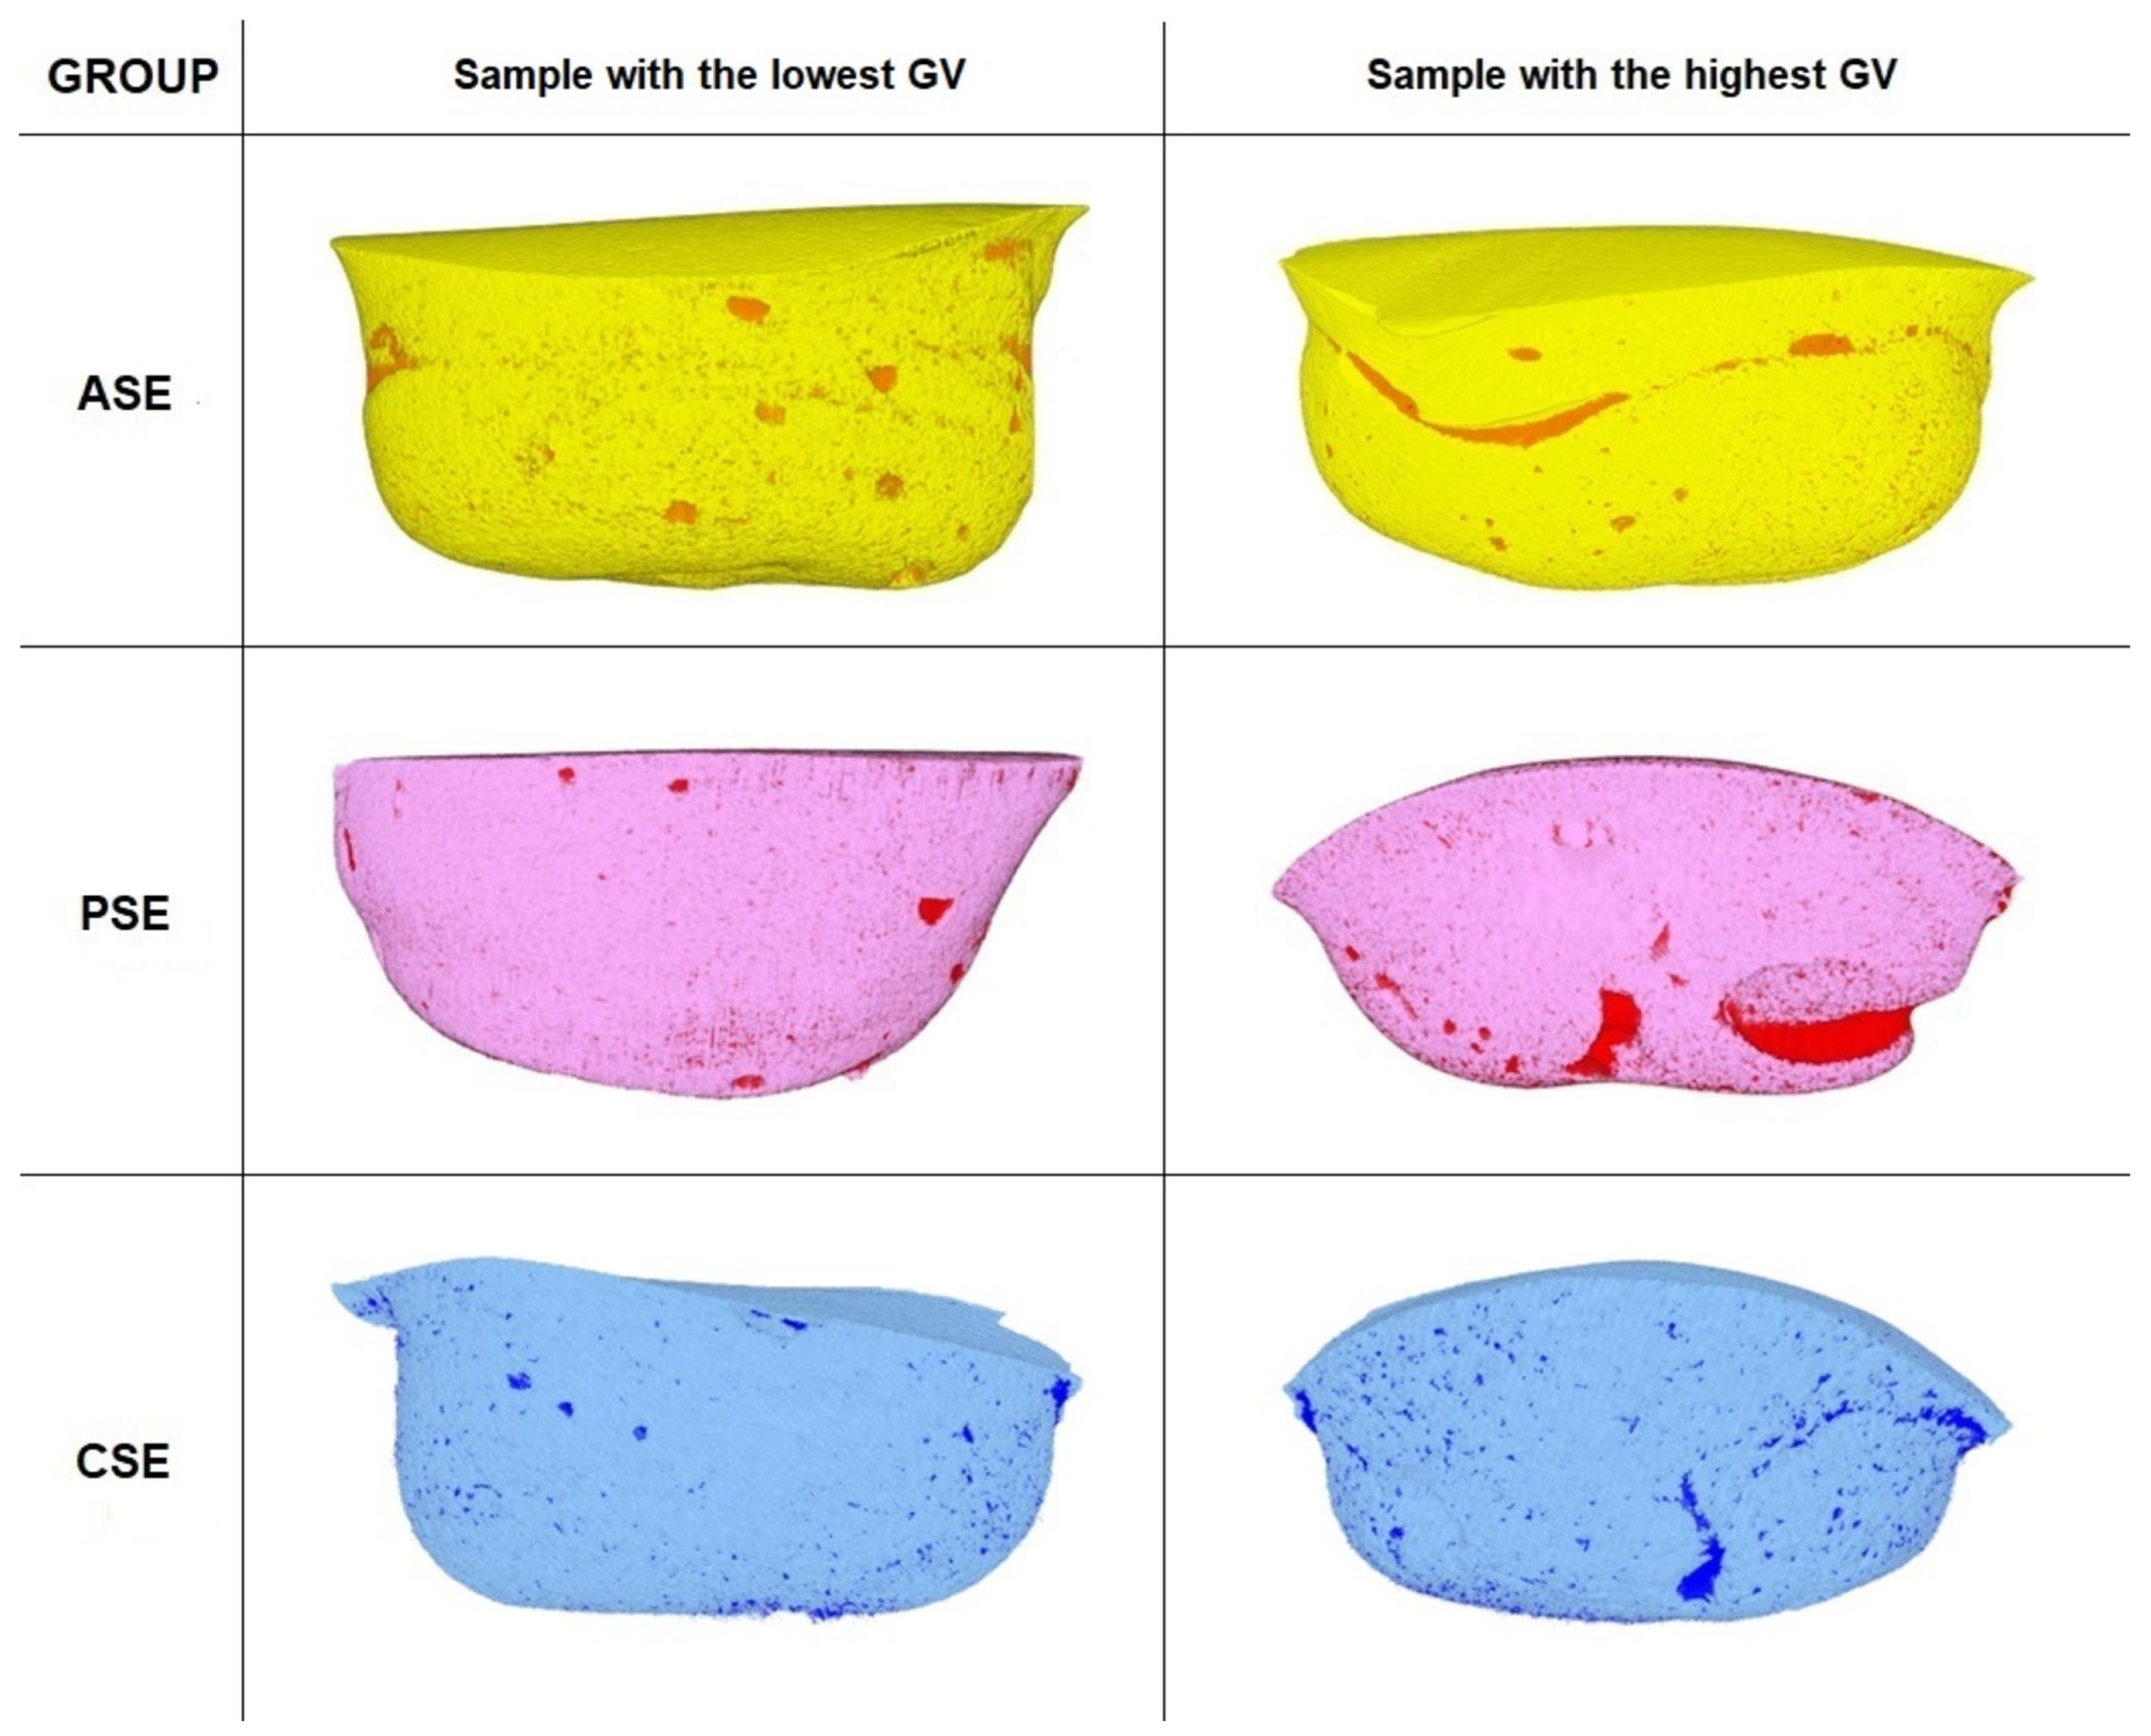

3.1. Gap Volume to Filling Volume (GV/FV) and Gap Volume to Cavity Volume (GV/CV) Ratios

4.3. Gap Volume to Filling Volume (GV/FV) and Gap Volume to Cavity Volume (GV/CV) Ratios